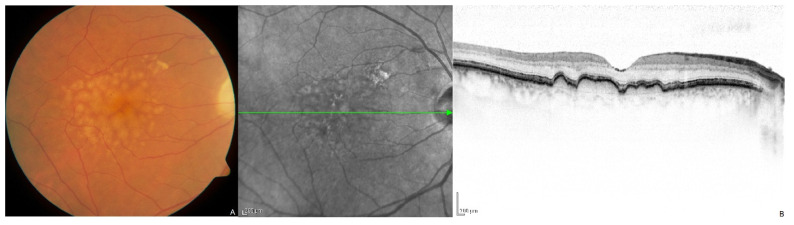

年齡相關(guān)性黃斑變性 (AMD) 的特征是黃斑區(qū)視網(wǎng)膜色素上皮 (RPE) 和/或視網(wǎng)膜下沉積物(分別稱為視網(wǎng)膜小疣或網(wǎng)狀假性視網(wǎng)膜小疣)的積聚,通常始于 70 歲以后(圖1 )。這會導(dǎo)致 RPE 進(jìn)行性退化,而 RPE 在維持其上層感光細(xì)胞健康方面發(fā)揮著關(guān)鍵的代謝和調(diào)節(jié)作用 。隨后局部感光細(xì)胞退化,導(dǎo)致中央視力逐漸喪失。

圖 1

圖 1.( A ) 一名 70 歲男性右眼黃斑視網(wǎng)膜黃斑硬化癥的彩色眼底照片。( B ) 黃斑視網(wǎng)膜黃斑硬化癥的光學(xué)相干斷層掃描圖像,顯示視網(wǎng)膜下色素上皮沉積物。。